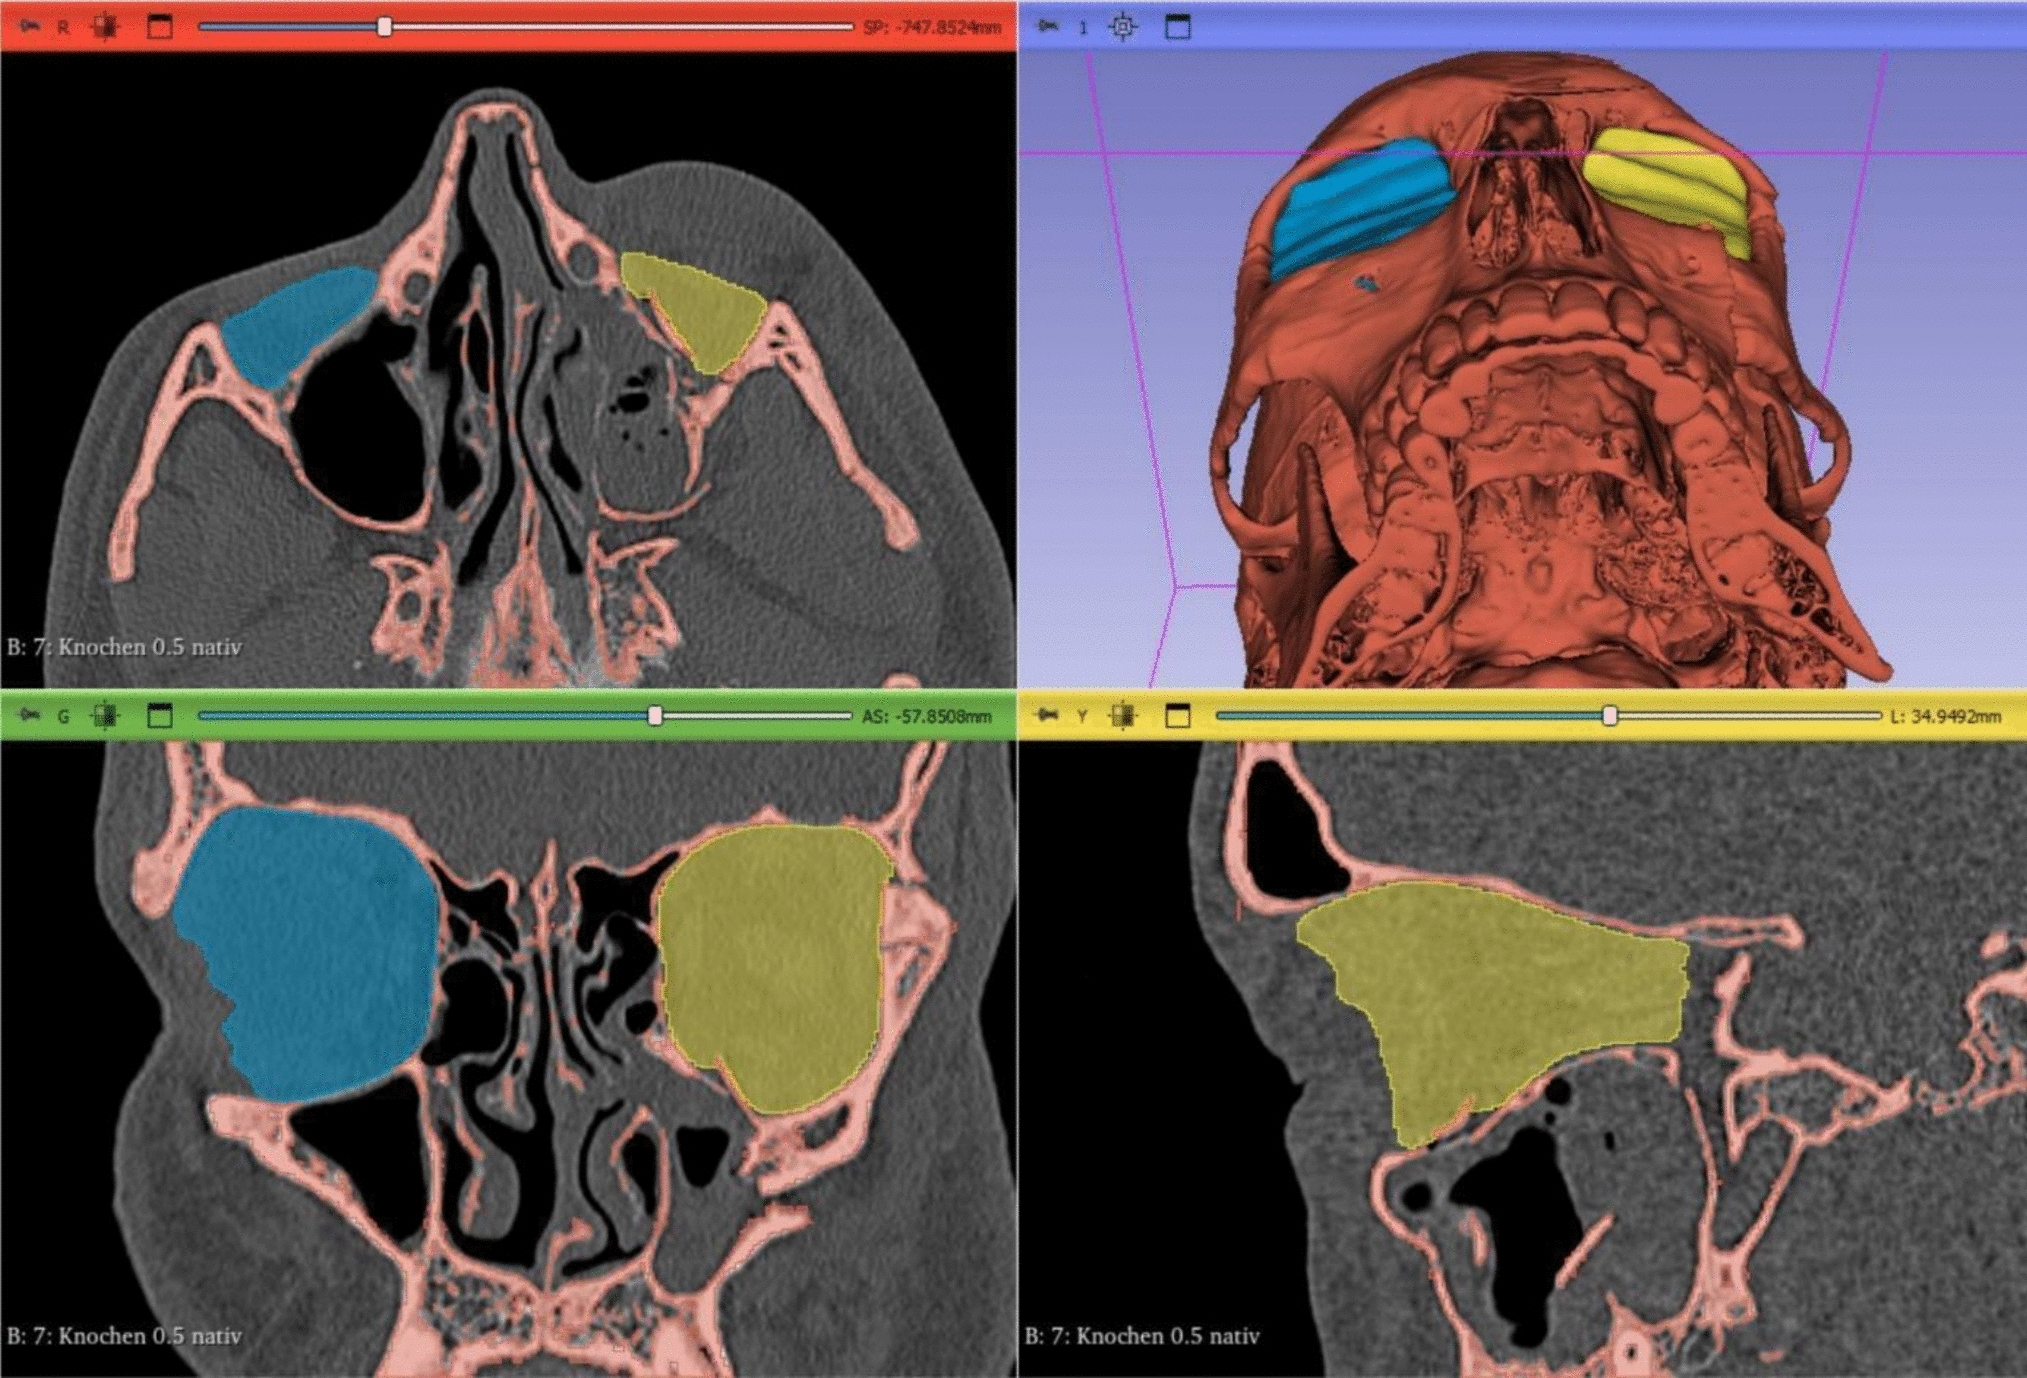

Fig. 2

Preoperative CT scan of the midface in axial (A), coronal (C), sagittal (D) and 3D reconstruction (B). Segmented volumes of fractured (yellow) and intact orbit (blue) were generated using 3D-Slicer software

A total of 46 patients underwent preoperative 3D imaging (CT or CBCT scans) to assess fracture severity and location. Post-operative imaging was performed as clinically indicated to assess implant position and fracture reduction in the same manner. The scans were then reconstructed as axial, coronal, and sagittal slices and transferred to a three-dimensional imaging software program (3D Slicer ver. 5.6.1, https://www.slicer.org/) [9].

The following anatomical landmarks were used to segment the orbital volume as previously described [10]: the anterior orbital rim was defined as a straight line connecting the posterior surface of the lacrimal sulcus and the lateral orbital rim. The posterior margin was defined as the orbital apex excluding the optic canal. The herniated orbital contents were included in the measurement of the orbital volume. Volumetric analysis was performed by an independent third-party analyst (m3i GmbH – I.Z.) who was not involved in the study design or had contact with the study patients. Software calibration was utilized to further adjust the contrast in the CT images to ensure accurate marking of the anatomical landmarks, and a manual segmentation as per standardized measurement protocols was carried out [11]. Additionally, a specialist in each center, blindly verified the volumetric measurements to further increase the reliability and eliminate any potential bias. The resulting volume was calculated for each orbit in cm3 and a three-dimensional image was generated (Figs. 2 and 3).